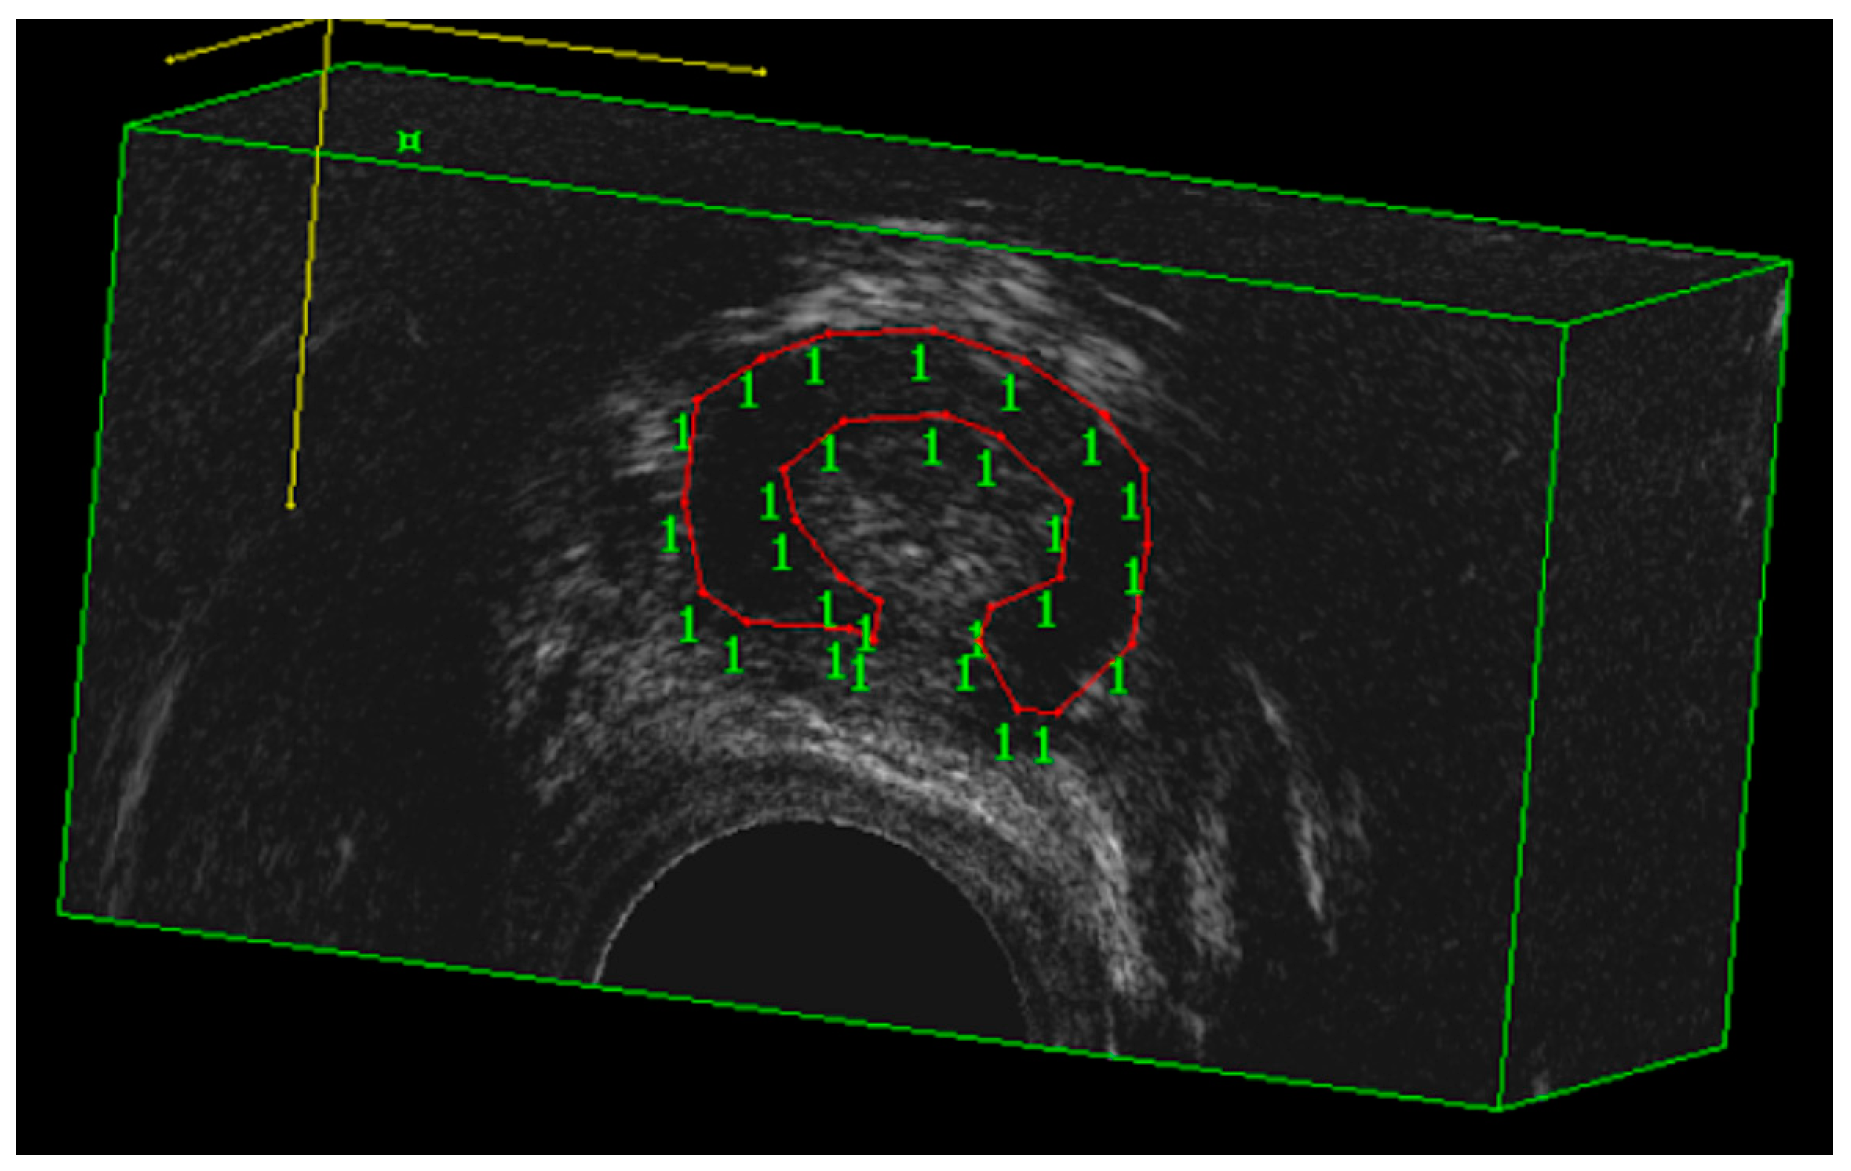

In addition to the quality-of-life tools, a volumetric assessment of the urethral rhabdosphincter (RS) was performed using a BK Flex Focus 400 sonographic machine equipped with a 9052 transducer by vaginal approach (BK Medical, Melegnano, Italy). This is a mechanical, single-element, multifrequency transducer with a built-in 3D acquisition system providing a 360° field of view over a longitudinal distance of 60 mm. Obtained volumes were assessed offline using the BK 3D Viewer 7.1 software in cubic mode. In this mode, the operator is able to perform volume measurements by delineating the margin of the RS on successive planes to achieve volume values (Figure 1).

Figure 1.

Volumetric assessment of the urethral rhabdosphincter (RS) using a BK Flex Focus 400 sonographic machine equipped with a 9052 transducer by vaginal approach.